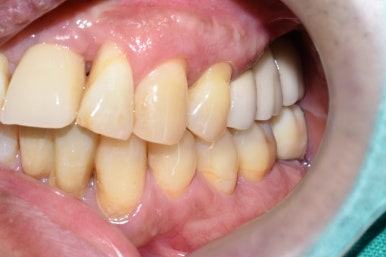

흔들리는 옆 치아와 흔들리는 임플란트를 제거하고 임플란트2개와 임플란트 브릿지로 마무리

흔들리는 옆 치아1개와 흔들리는 임플란트2개를 제거하고

3개의 자리를 임플란트2개와 가짜머리1개가 있는 임플란트 브릿지로

3개의 자리를 마무리하였습니다.

1.흔들리던 임플란트 2. 임플란트 제거 후 3.임플란트 재수술 후

1과 2 임플란트 모두 제거하고

새로 임플란트를 심어 완성하였습니다.